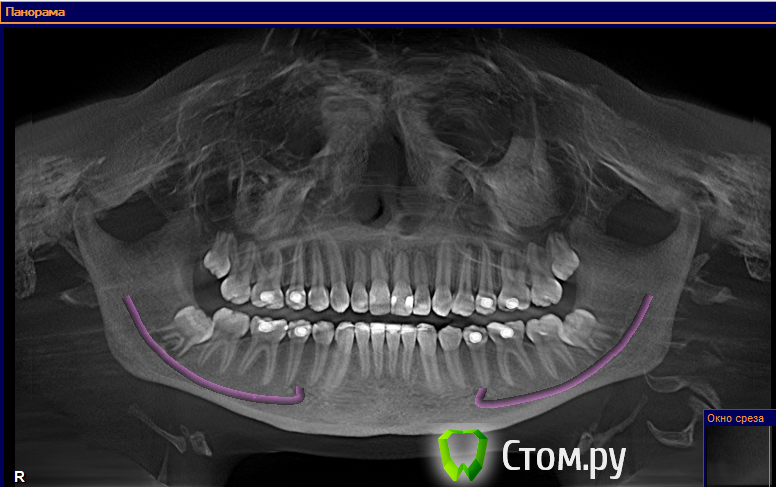

ElenaV Опубликовано 29 июня, 2014 Поделиться Опубликовано 29 июня, 2014 (изменено) Здравствуйте, дорогие доктора! У моей дочери 16ти лет проблема с ВНЧС. При ношении брекетов ей вытягивали нижнюю челюсть, выравнивали прикус и зубы , в частности - клыки выпирающие выравнивали. А через 1,5 года после снятия в одно прекрасное утро не смогла открыть рот. Нам советовали делать лазер, становилось легче. Так было 2 раза. А теперь по утрам, если спит на правой щеке, то челюсть правую заклинивает. Голова сильно болит в висках. Связано ли это с брекетами или другая причина может быть? У нас в Красноярске мы нашли доктора, который собрался нам помочь, поставить шины http://astreja.ru/uslugi/neyro-myshechnaya-stomatologiya. Может ли шина помочь решить эту проблему? В Красноярске выбор докторов небольшой, можно сказать - его нет. И уже просто страшно становится. Читая в интернете об этой проблеме, поняла, что это дело очень тонкое и непростое, испортить жизнь ребенку можно запросто. А еще советуют мануального терапевта. Куда пойти ? Может ли мануальный терапевт решить эти проблемы? Знакомый стоматолог сказал, что если челюсть поправят, то прикус может нарушится. А мануальный говорит - приходите - все исправим, даже снимков ему не надо. Теперь хочу выяснить у специалистов, как все таки поступить. К кому пойти сначала. Очень Вам буду благодарна за совет.Дорогие доктора, можете подсказать, что с суставом? Доктор сказал, что сустав находится далеко от височной кости, т.е. расстояние больше чем норма. Напишите, пожалуйста, что Вы видите на снимке, какую патологию. Вот еще сделала скриншоты суставов: левый и правый Вот еще правый сустав, немножко по другому Изменено 29 июня, 2014 пользователем ElenaV Ссылка на комментарий

Skip Опубликовано 29 июня, 2014 Поделиться Опубликовано 29 июня, 2014 Напишите, пожалуйста, что Вы видите на снимке, какую патологию. Эти КТ, с полуоткрытым ртом и выдвинутой челюстью, мало о чём говорят. У вас там что, уже стоит шина? Ссылка на комментарий

ElenaV Опубликовано 30 июня, 2014 Автор Поделиться Опубликовано 30 июня, 2014 (изменено) Эти КТ, с полуоткрытым ртом и выдвинутой челюстью, мало о чём говорят. У вас там что, уже стоит шина?Шины еще нет, мы сходили на прием, советуют ставить шину. Это КТ в 3Д делали с пластиной во рту, сказали - так надо. Что обычно так делают.Может поэтому и кажется доктору, что сустав неправильно в лунке стоит? Доктор сказал, что сустав далеко стоит от нормального местоположения. Поэтому выскакивает.Нужно МРТ сделать что бы точно понять? Или КТ переделывать? Изменено 30 июня, 2014 пользователем ElenaV Ссылка на комментарий

Force Опубликовано 1 июля, 2014 Поделиться Опубликовано 1 июля, 2014 с восковым шаблоном это по Маклафлину в ЦС сделано КТ. 1 Ссылка на комментарий

Skip Опубликовано 1 июля, 2014 Поделиться Опубликовано 1 июля, 2014 с восковым шаблоном это по Маклафлину в ЦС сделано КТ. Понятно. Ну тогда и с привычной окклюзией стоило бы сравнить, т.е. два снимка, а вернее три, если добавить макс. открытие рта. 1 Ссылка на комментарий